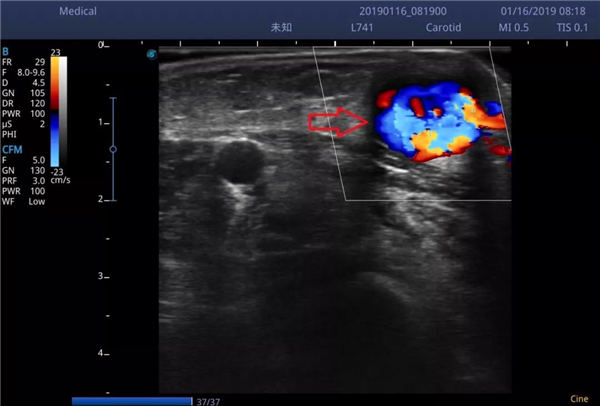

经过一天一夜的持续泵入尿激酶溶栓治疗,谭老先生贵要静脉内的血栓完全溶解,血流充盈整个血管、血流量大,完全可以满足透析需求。

虽然超声仍可见桡动脉(红色箭头)、贵要静脉(蓝色箭头)、内瘘口(黄色箭头)存在轻度狭窄↓↓↓,但血流通畅不影响透析。